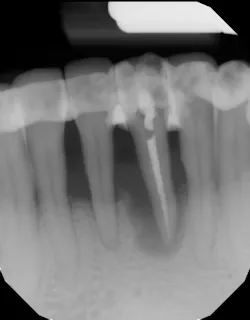

- Ensure tooth does not have a root fracture and check/refer for endodontic treatment if tooth is nonvital (figure 1)